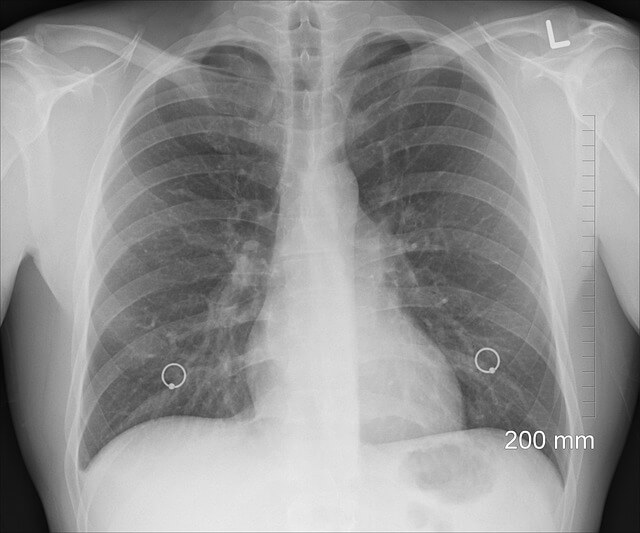

첫째, 엑스레이를 촬영해 흉부에 염증이 있는지 확인합니다.